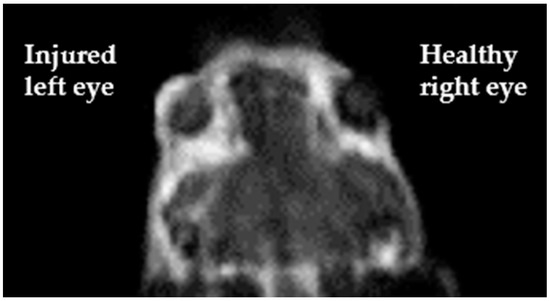

- Joshi, V.P.; Vaishnavi, K.S.; Ojha, S.K.; Singh, V.; Basu, S. A reliable animal model of corneal stromal opacity: Development and validation using in vivo imaging. Ocul. Surf. 2020, 18, 681–688. [Google Scholar] [CrossRef]